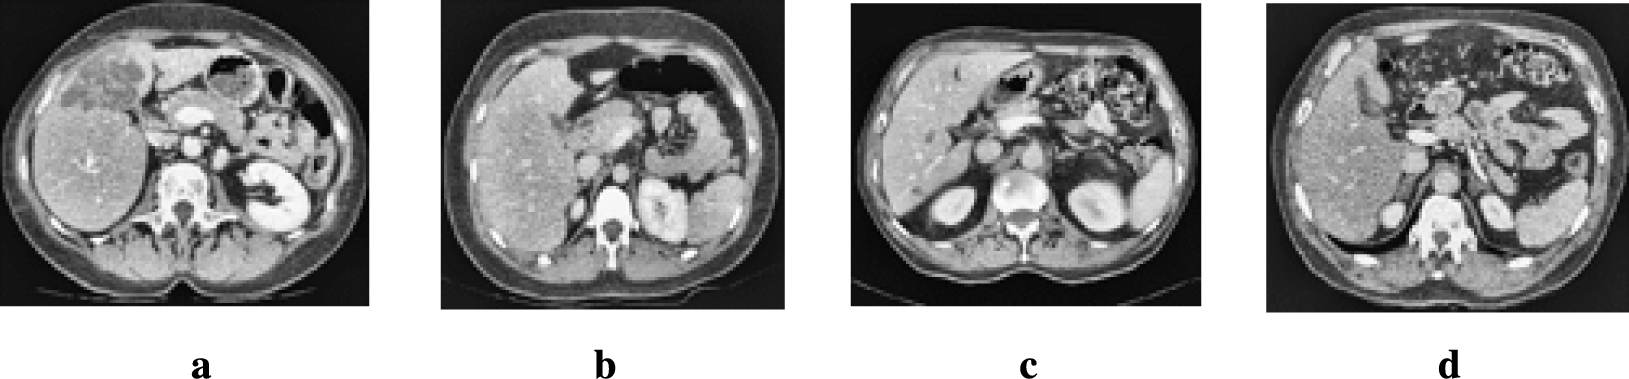

Fig. 9

From: Liver CT image segmentation network based on multi-scale feature fusion